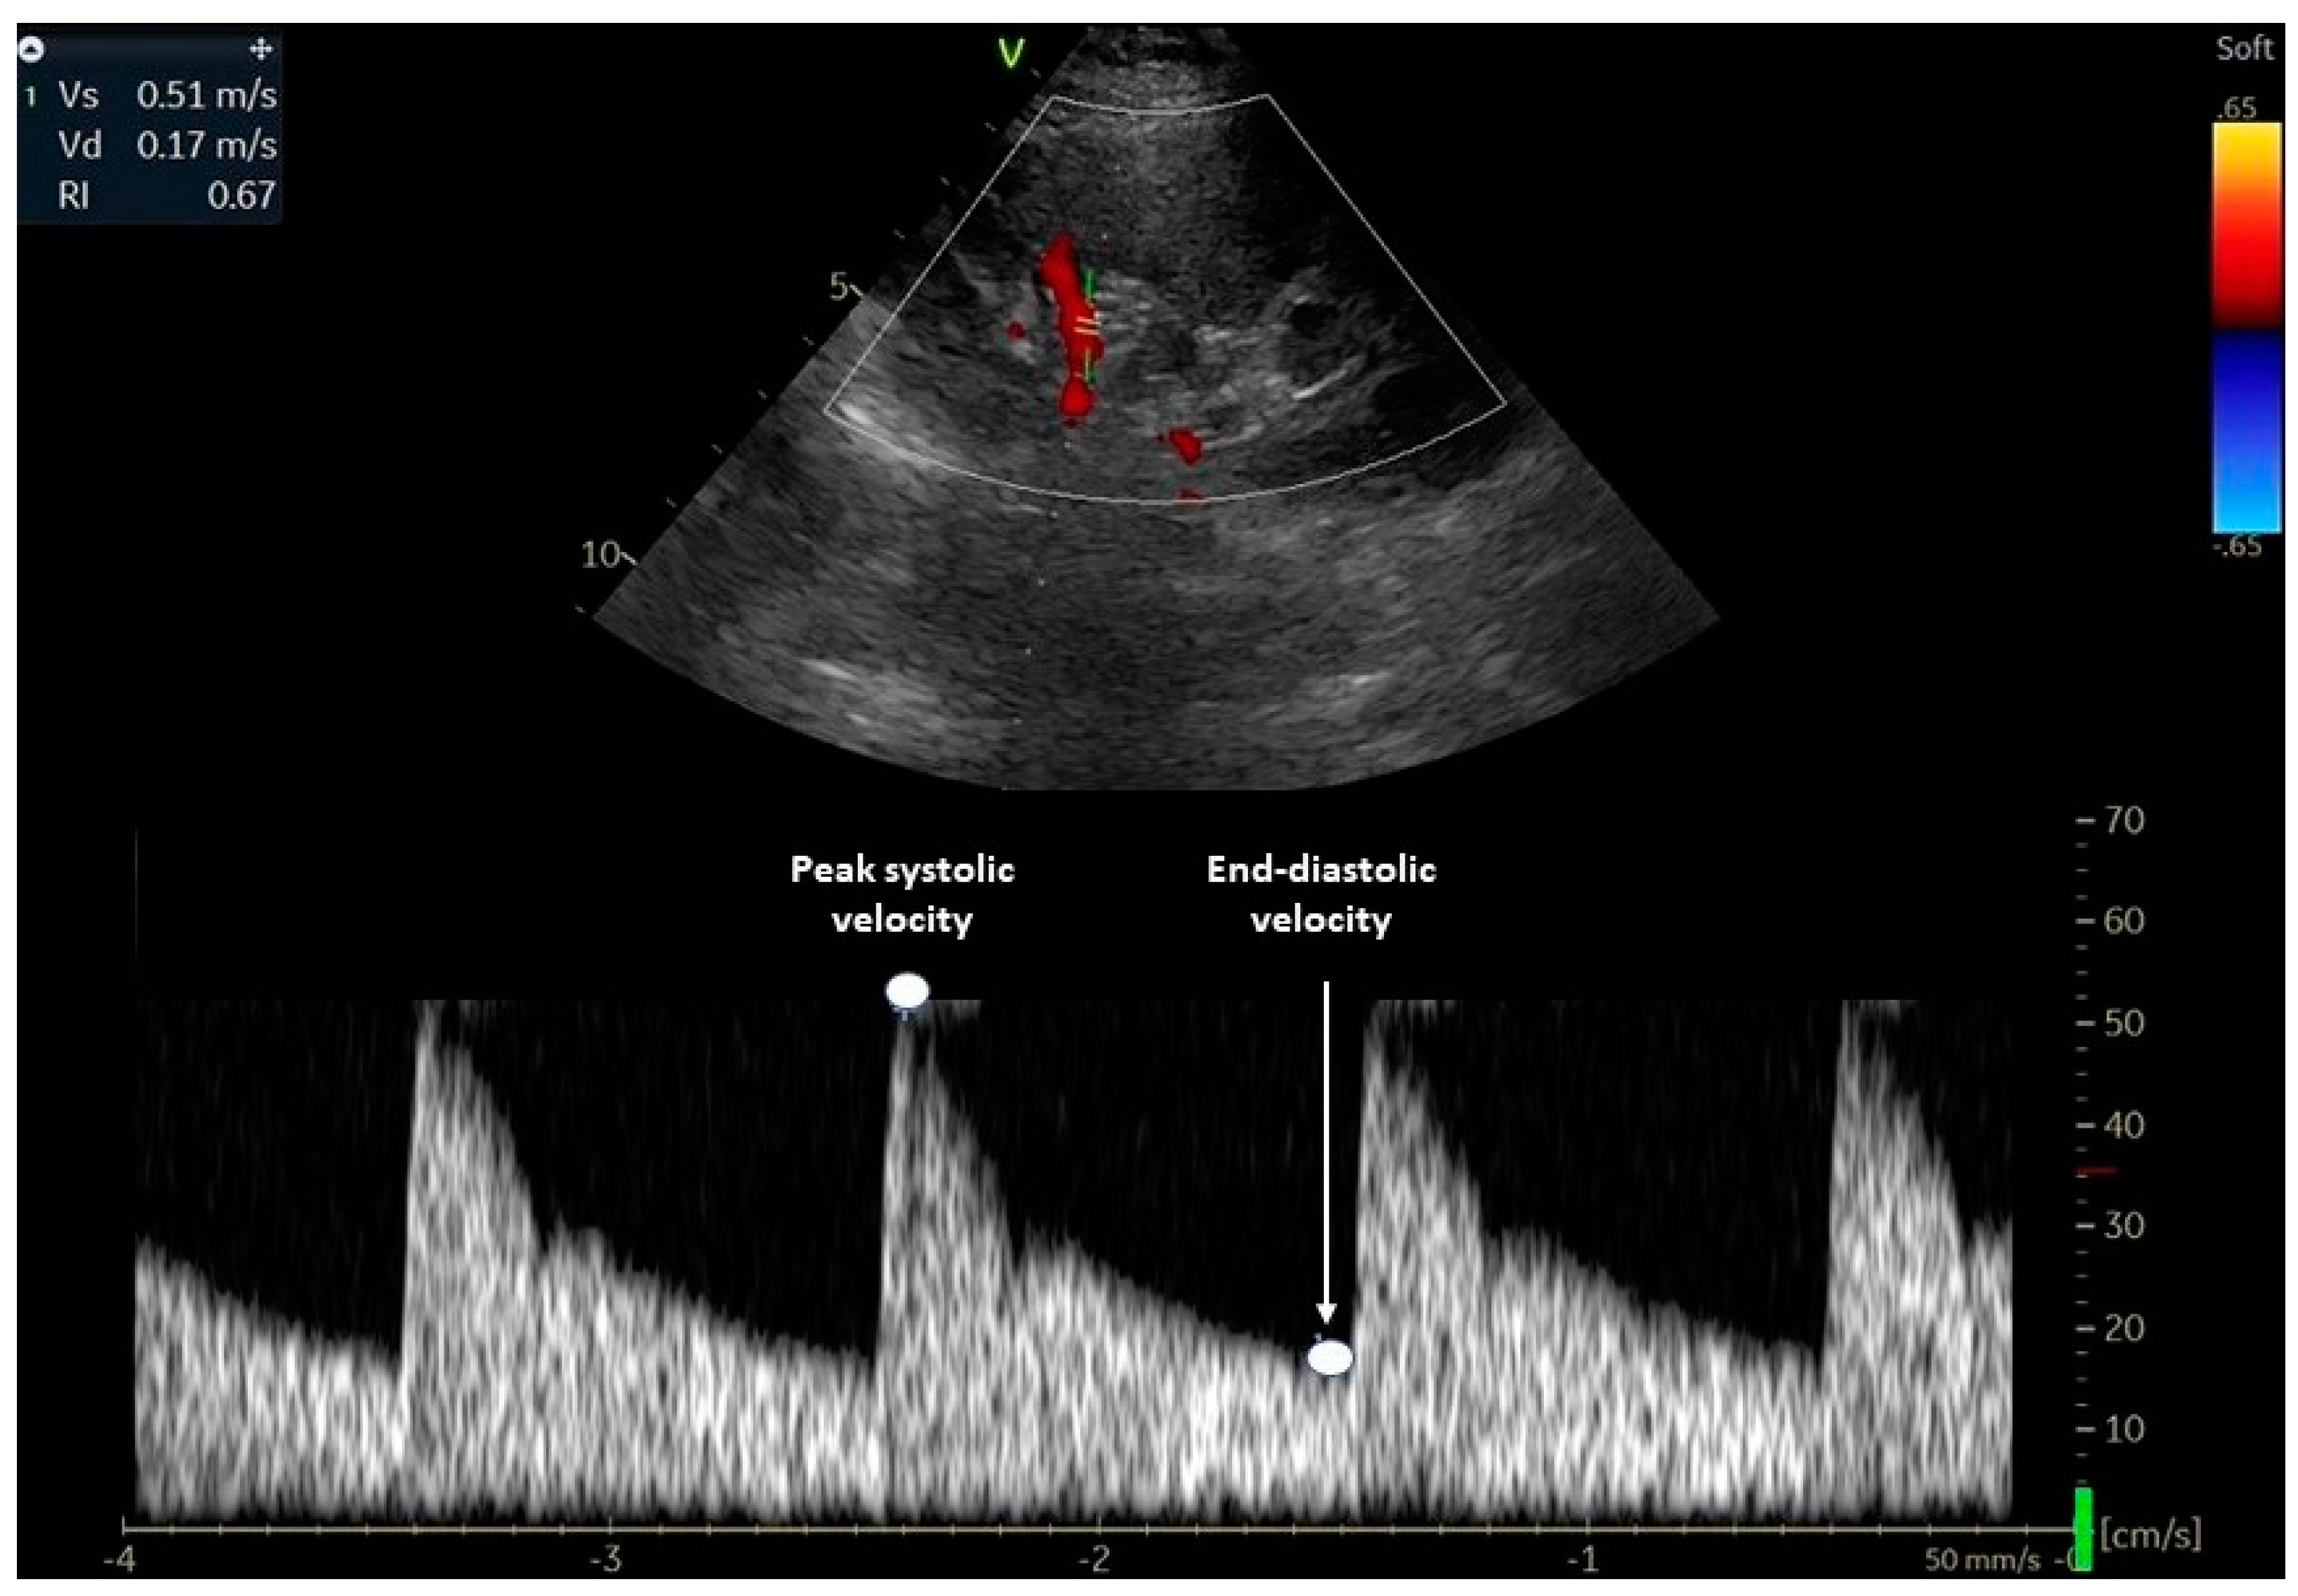

Figure 1 illustrates how RRI is assessed using a Doppler ultrasound waveform at the level of a renal interlobar artery.

Figure 1.

Evaluation of the renal resistive index using Doppler ultrasound. The transducer is placed in an interlobar artery and the spectral Doppler examines the peak systolic and end-diastolic velocities. The renal RI is calculated using the following formula: (peak systolic- end-diastolic)/ peak systolic. RI: resistive index.